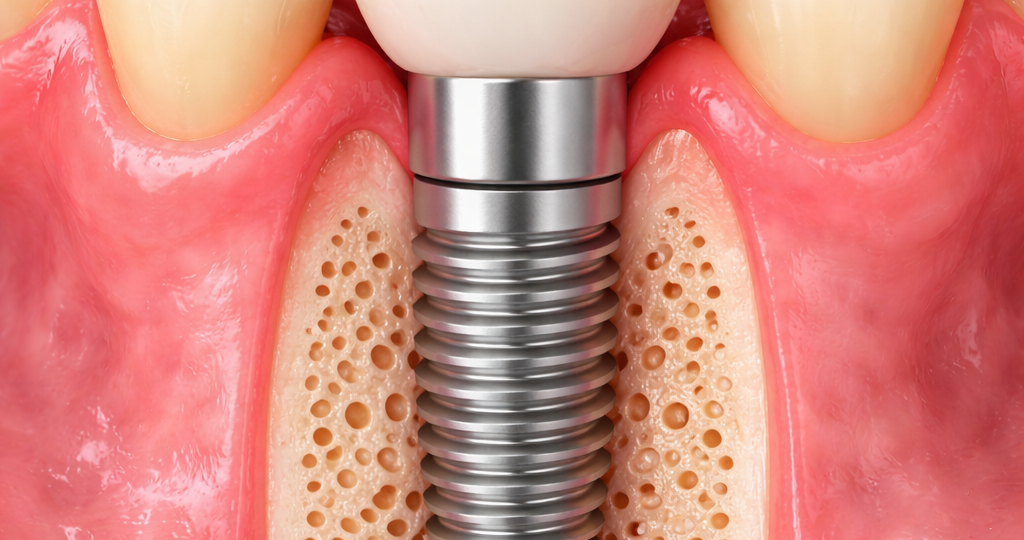

O implante dentário é uma estrutura de titânio posicionada no osso maxilar ou mandibular com o objetivo de substituir a raiz de um dente perdido. Sobre ele, posteriormente, é instalada uma prótese que devolve forma, função e harmonia ao sorriso.

Diferentemente de soluções removíveis, o implante atua de forma integrada ao organismo, permitindo maior estabilidade mastigatória e preservação óssea.